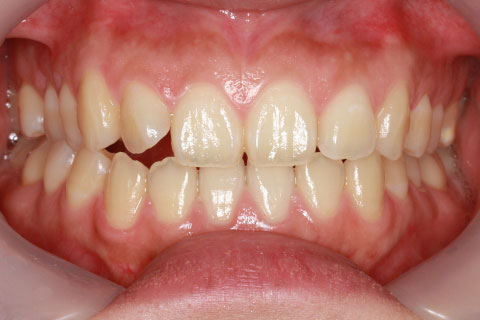

オールセラミックの症例7

前歯2本のねじれをジルコニアセラミックスで治療。

- 年齢・性別

- 17歳女性

- 治療期間

- 1ヶ月

- 抜歯

- なし

- 治療費

- 35.2万円

- 備考

- 前歯4本の歯列不正によるセラミック治療

- 治療内容

- 歯質を削除し、セラミック冠をセメント合着

- 施術の副作用(リスク)

- 知覚過敏、歯髄炎、荷重負担